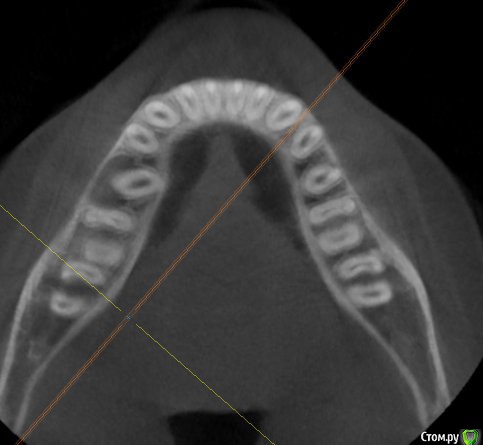

Kovalov Igor Опубликовано 14 июля, 2015 Поделиться Опубликовано 14 июля, 2015 (изменено) Уважаемые коллеги приветствую Вас! Встал вопрос стоит ли трогать фолликулярную кисту или наблюдать?Пациентка моя сестра, фолликулярная киста была случайной находкой, обнаружил ортодонт, отправил в областную больницу г. БелгородаВ детской ЧЛХ отказались, отправили в Харьков, это был 2013 год ещё. Во взрослой ЧЛХ не взялись, по возрасту. В детской члх сделали КТ, снимки и панораму прилагаю.Ps: картина за 2 года стала получше, но КТ сделают позже, есть внеротовой Rg снимок. Дело в том что я живу от сестры более 3000 км., сам бы это дело вскрыл амбулаторно, цистэктомия, графт+мембрана если гноя не будет... либо под йодоформом. Но вопрос стоит ли? и как по протоколу, каков Ваш план лечения? Депульпировать ли зубы 45-46? Изменено 14 июля, 2015 пользователем Kovalov Igor Ссылка на комментарий

Kovalov Igor Опубликовано 14 июля, 2015 Автор Поделиться Опубликовано 14 июля, 2015 вот Rg свежий. Вроде граница фолликулярной кисты уменьшилась.Как сделают КТ поделюсь тут... Буду признателен за ответы! Ссылка на комментарий